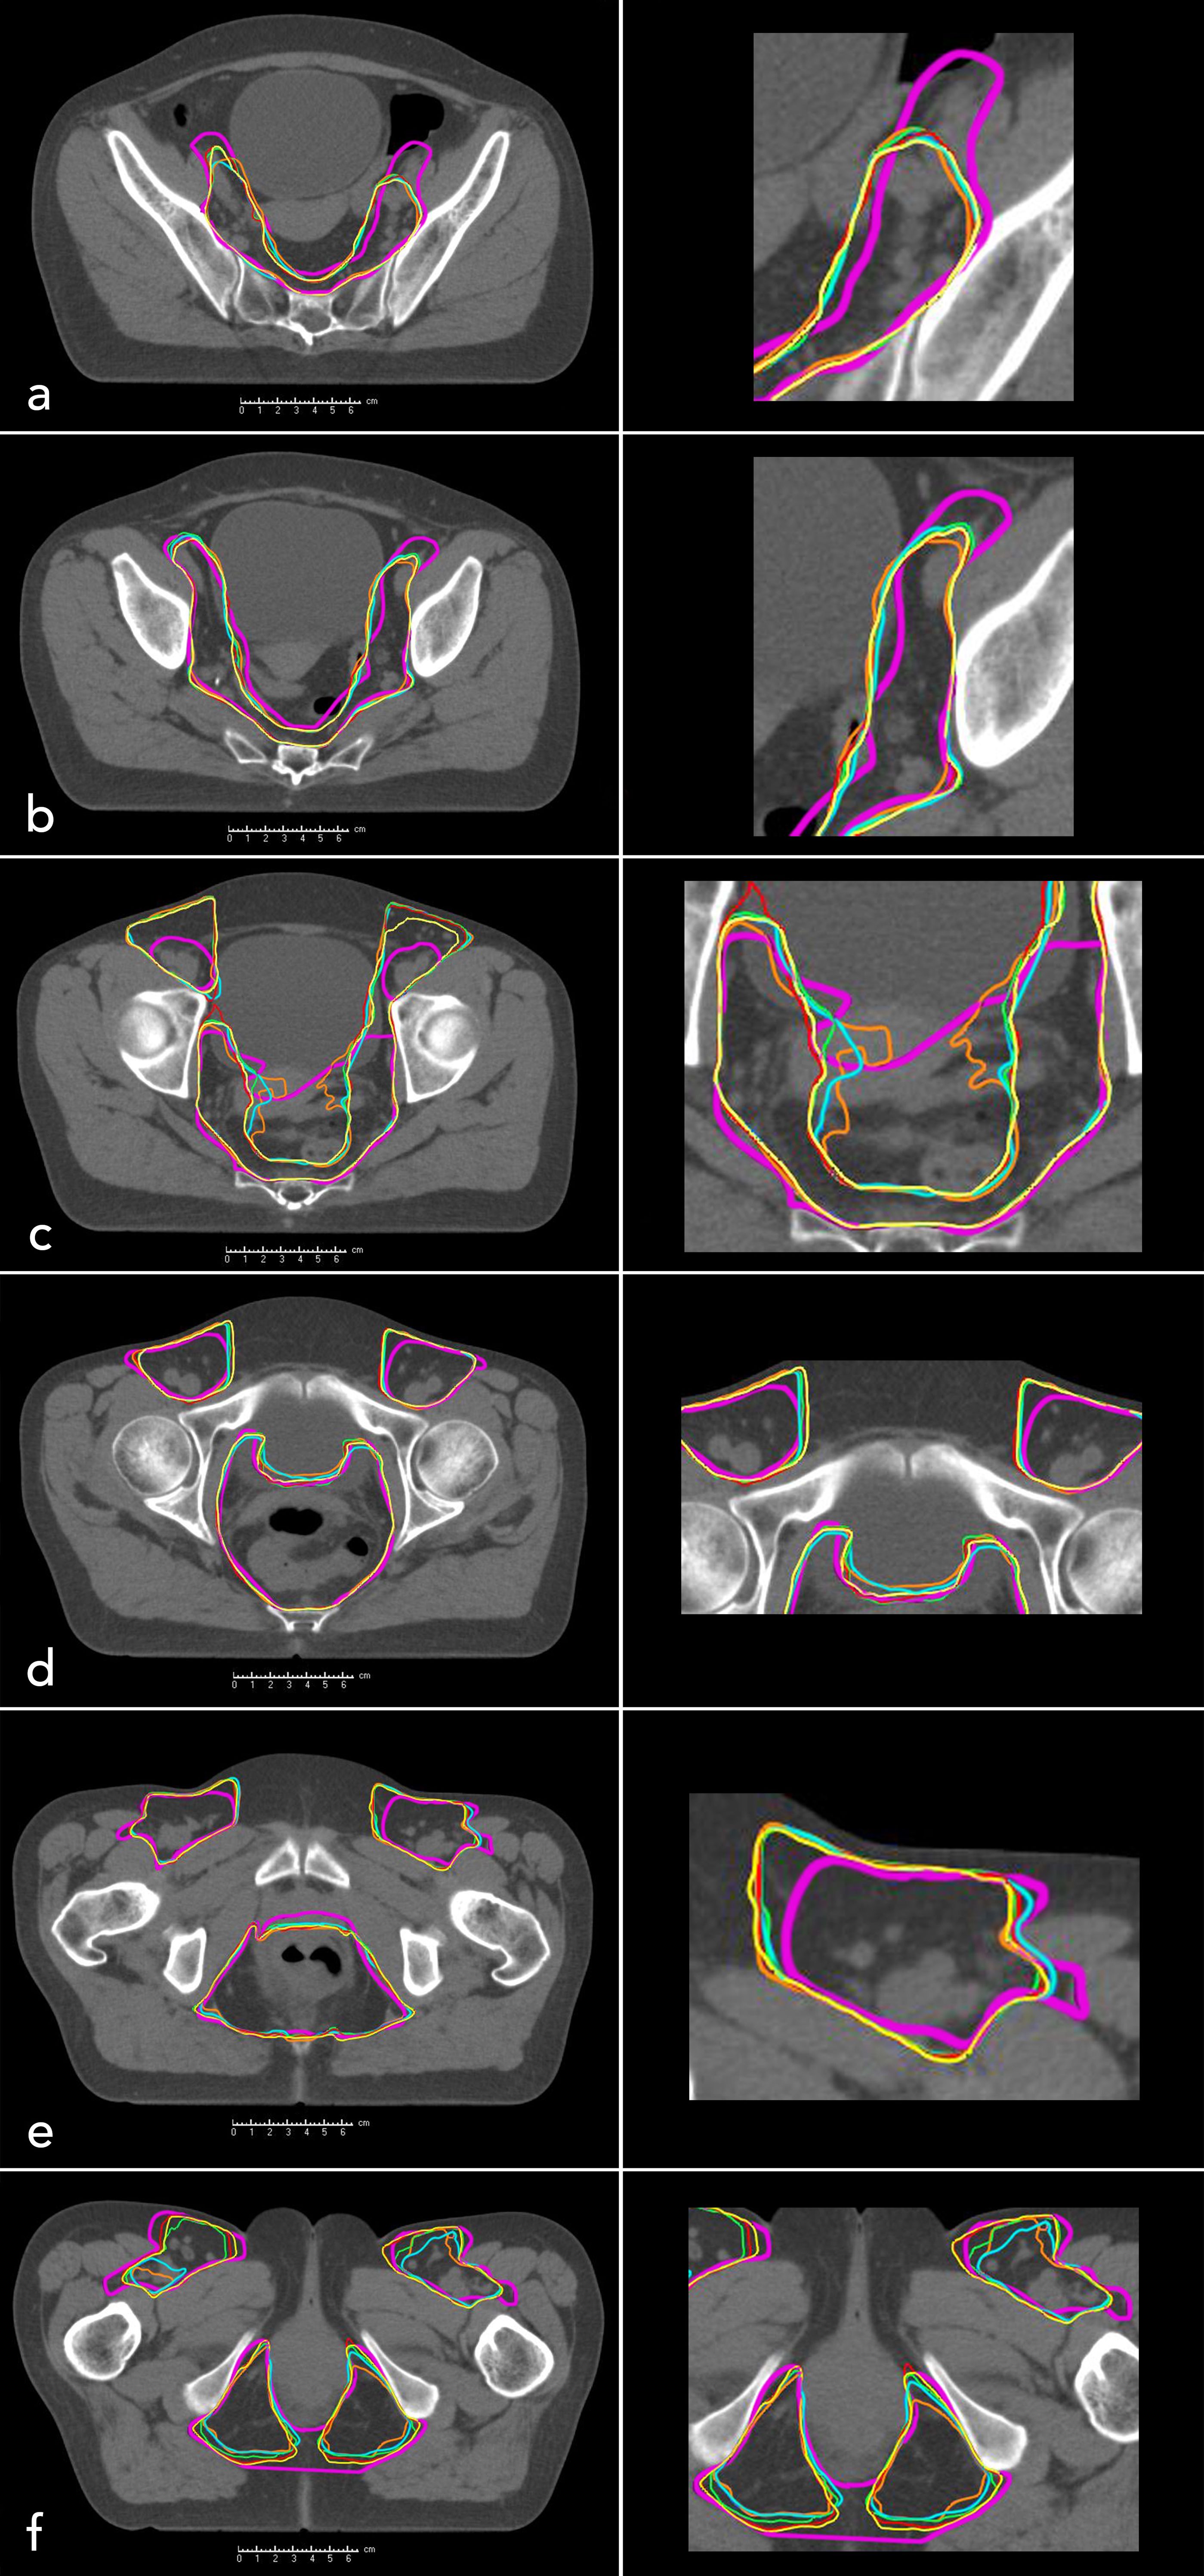

In the context of radiation planning, 29 patients were initially classified as FDG-positive (N-Stage ≥1). However, two of these patients showed doubtful FDG-positivity and were therefore reclassified as N-Stage 0 for this study. Consequently, 27 of 51 patients (52.9%) were considered FDG positive. Among these, a median number of two LNs showed an increased FDG-uptake. FDG-positive LNs were most frequently located in the inguinal region (77.8%, N=21), followed by the external and internal iliac (29.6%, N=8, respectively), the mesorectal (25.9%, N=7) and presacral space (18.5%, N=5). Figure 2 provides a representative visualization of CTV contours across different atlas sizes, displayed on selected CT slices, highlighting the variations in segmentation accuracy as the atlas size increases.

Figure 2

Composite image depicting six axial CT scan sections of the pelvis, labeled (a) to (f), arranged from cranial to caudal levels. Each section includes superimposed, color-coded contours representing clinical target volumes. Automatically generated volumes are displayed in orange (n = 10), blue (n = 20), green (n = 30), red (n = 40), and yellow (n = 50). The manually contoured clinical target volume (mCTV) is highlighted in purple for patient 1. Close-up views illustrate detailed contour overlap and variation.

Figure 2. Manually contoured clinical target volume (mCTV, purple, patient 1) and automatically generated clinical target volumes for different atlas sizes: n = 10 (orange), n = 20 (blue), n = 30 (green), n = 40 (red), n = 50 (yellow). Axial CT slices of the pelvis are shown from cranial to caudal levels: (a–f).